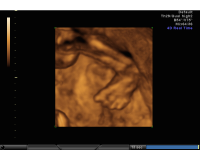

Clubbed foot 3D skeleton